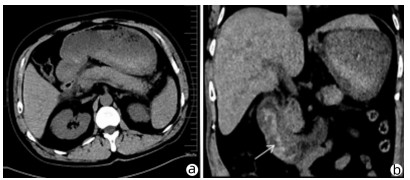

Clinical effect of simultaneous surgical resection of hepatic and pancreatic lesions versus systemic chemotherapy in treatment of resectable pancreatic cancer with liver metastasis

Abstract(1384) HTML (1170) PDF (2734KB)(54)

Objective  To investigate the clinical effect of simultaneous surgical resection of hepatic and pancreatic lesions versus systemic chemotherapy in treatment of resectable pancreatic cancer with liver metastasis (PCLM).  Methods  A retrospective analysis was performed for related data of the patients with PCLM who were admitted to Shengjing Hospital of China Medical University from January 2013 to May 2020, and the patients with resectable PCLM were screened out and then divided into surgery group and chemotherapy group. The propensity score matching (PSM) method was used to reduce the impact of data bias and confounding factors. The independent samples t-test or the Mann- Whitney U test was used for comparison of continuous data between two groups, and the chi-square test was used for comparison of categorical data between two groups. The Kaplan-Meier method was used to calculate survival time, and the log-rank test was used for evaluation. The univariate and multivariate Cox regression models were used to investigate the independent risk factors for survival.  Results  A total of 56 patients with resectable PCLM were screened out, with 33 patients in the surgery group and 23 patients in the chemotherapy group, and there were 15 patients in each group after PSM. The surgery group had a significantly shorter median overall survival time than the chemotherapy group before PSM (6.6 months vs 10.4 months, χ2=4.476, P=0.034) and after PSM (6.4 months vs 10.5 months, χ2=4.309, P=0.038). The multivariate Cox regression analysis showed that poorly differentiated tumor (hazard ratio [HR]=4.945, 95% confidence interval [CI]: 1.980-12.348, P=0.001) and absence of postoperative chemotherapy (HR=3.670, 95%CI: 1.437-9.376, P=0.007) were independent risk factors for poor prognosis in patients with PCLM.  Conclusion  Compared with chemotherapy, simultaneous surgical resection of hepatic and pancreatic lesions fails to prolong the overall survival time of patients with resectable PCLM. Patients with poorly differentiated tumor and those without postoperative chemotherapy tend to have poor prognosis.